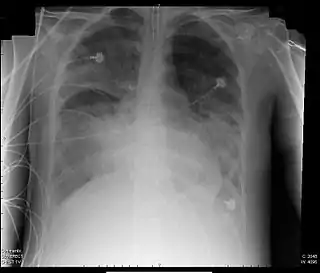

![]() Radiografía de tórax de paciente con SDRA | ||

El síndrome de dificultad respiratoria aguda (SDRA),[1] también denominado síndrome de distrés respiratorio agudo (en inglés: acute respiratory distress syndrome, ARDS), fue descrito por Ashbaugh y colaboradores en 1967, describiendo a doce pacientes con taquipnea, hipoxemia refractaria y opacidades difusas en radiografía de tórax después de infección o trauma.[2] Está definido actualmente como una insuficiencia respiratoria grave, debida a edema pulmonar, no cardiogénico, causado por aumento de la permeabilidad de la barrera alvéolo-capilar y secundario a daño pulmonar agudo. Cuatro definiciones mayores de SDRA han evolucionado sobre los años.

SDRA fue definido en términos del ratio o cociente entre la presión parcial de oxígeno arterial (PaO2) y la fracción de oxígeno inspirada (FiO2) por debajo de 200 mmHg, y la presencia de infiltrados alveolares en la ex de tórax. Estos infiltrados pueden parecer semejantes a los vistos en la insuficiencia cardíaca con edema pulmonar, pero la silueta cardíaca (tamaño) es normal en el SDRA. También la presión de enclavamiento pulmonar es normal (por debajo de 18 mmHg) en el SDRA, estando aumentada en caso de edema pulmonar cardiotónico.[6]

| Opacidades bilaterales que son "consistentes con edema pulmonar" en radiografía de tórax o TC de tórax. | Existe poca fiabilidad interobservador en interpretar la Rx de tórax por la presencia de edema. Para dirigir este asunto, la definición de Berlin ofrece criterios más explícitos (ejemplo; opacidades no deben ser completamente explicadas por derrame, atelectasia lobar o pulmonar, o nódulos o masas), con radiografía ilustrativa proporcionada. |